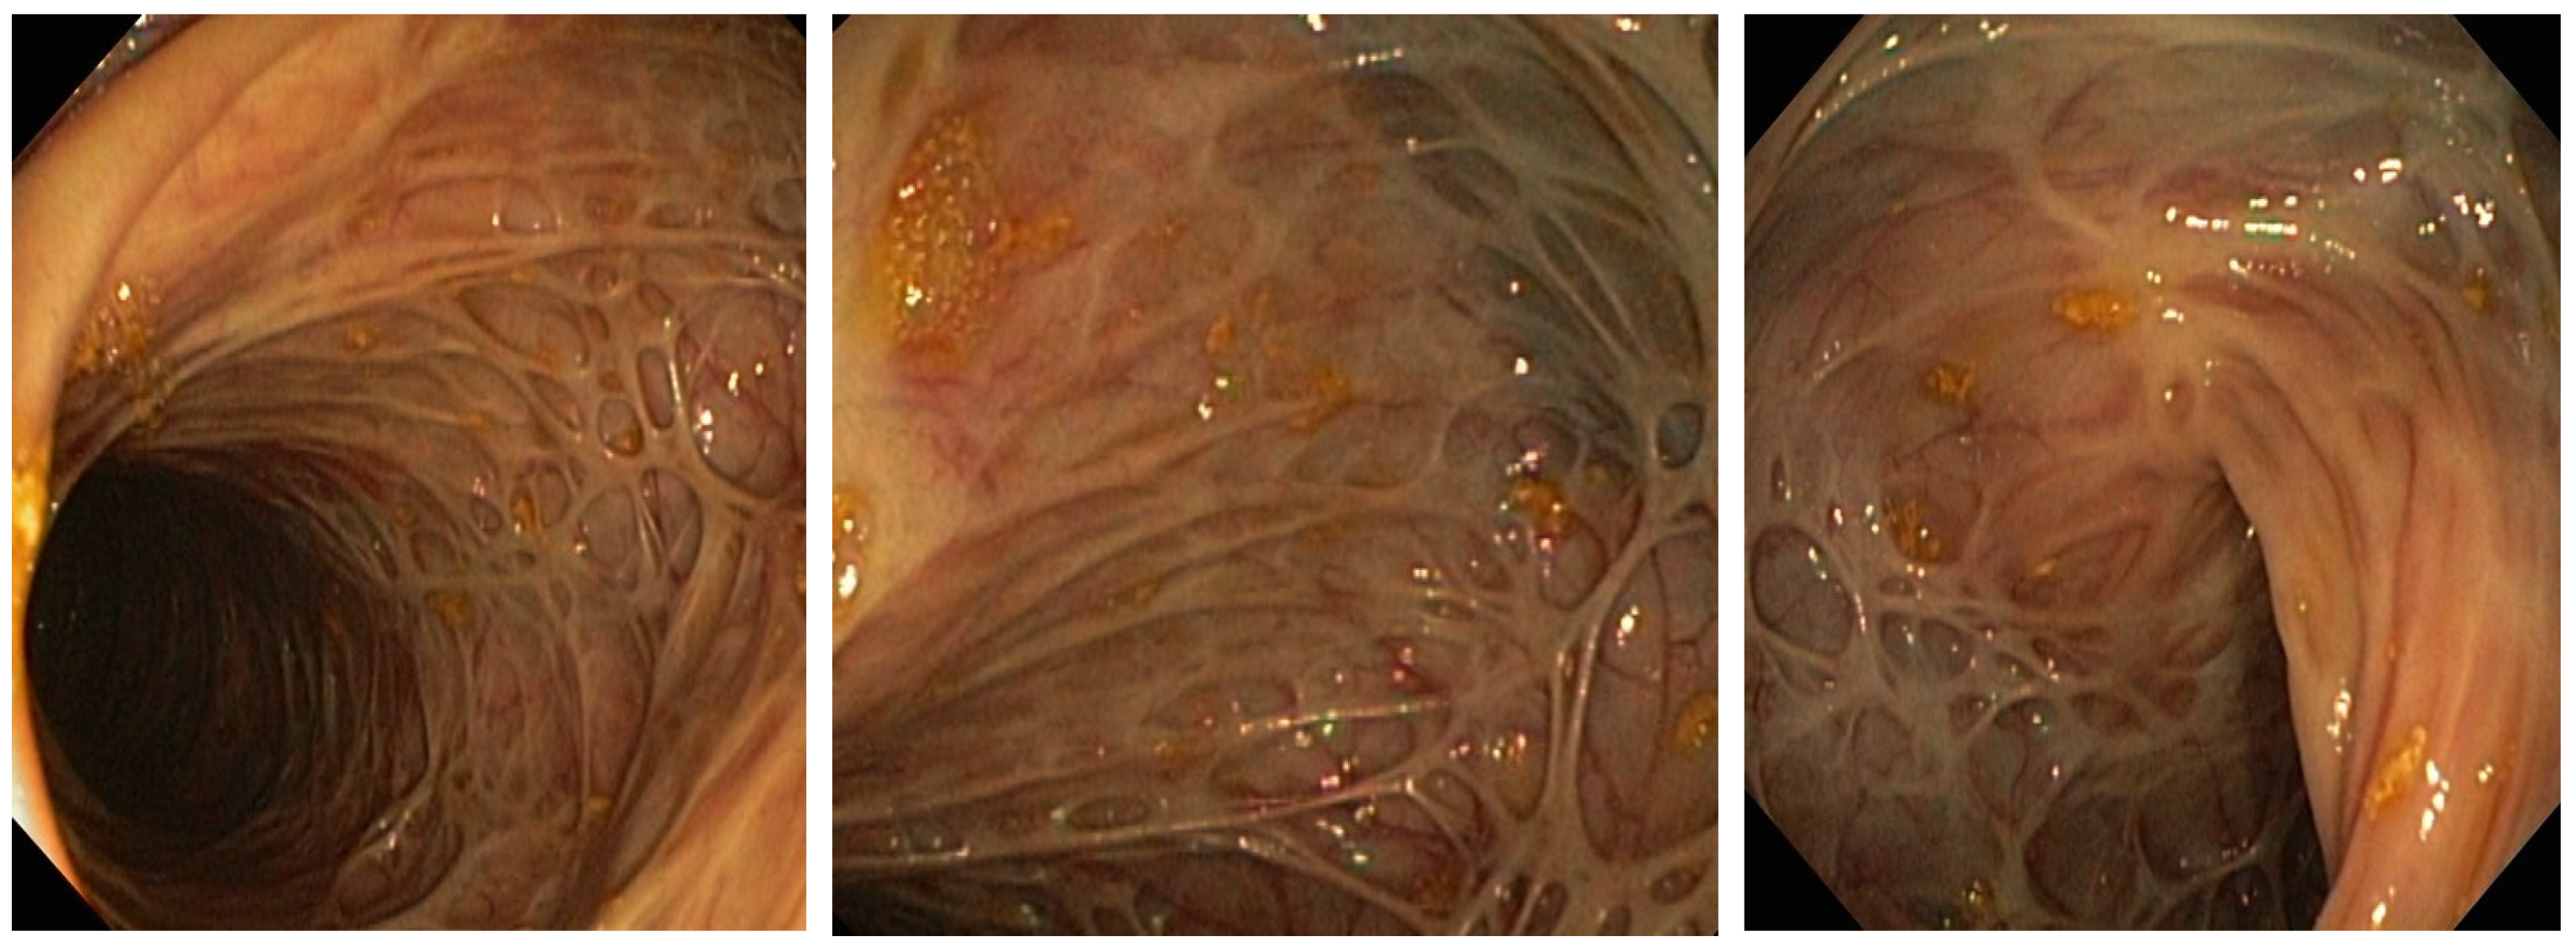

In August 2016, a 36-year-old woman presented to the emergency room (ER) of a regional hospital with a 10-day history of diarrhea (up to 5 bowel movements/24 h with occasional hematochezia), abdominal pain, fever (up to 38 C), weakness, chills, vomiting, and altered state of consciousness. During the previous 3 months, she intentionally lost 15 kg. Namely, the patient weight was 88 kg with a body mass index (BMI) of 29.1 when she started the nutritionist-prescribed diet, and afterwards her BMI was 24.1 and her weight reduced to 73 kg. Three weeks before admission, a self-limiting episode of high fever and diarrhea occurred. The patient personal history was negative for chronic diseases, operations, and allergies to medication. The patient denied intake of herbal or non-prescribed medication. Initial vitals gathered in the ER were as follows: blood pressure 90/60 mmHg, pulse 110 beats/minute. Physical examination showed tenderness of both lower quadrants of the abdomen, and chest auscultation identified decreased sounds in the lower right lung field. Laboratory investigations performed on the day of admission showed low hemoglobin (Hgb 35 g/L), mean cell volume (MCV 97 fL), mean corpuscular hemoglobin concentration (MCHC 252 g/L), significant reticulocytosis (15.8%), leukocytosis (45.5 × 109/mL), and thrombocytosis (538 × 109/mL), together with low serum protein (49 g/L), low albumin (18 g/L), and low potassium (2.8 mmol/L), increased lactate dehydrogenase (LDH 1218 U/L), low haptoglobin (0.07 g/L), total bilirubin of 43 umol/L, and direct bilirubin of 16 umol/L. Ferritin was increased to 1130 mcg/mL, while vitamin B12 (147 ng/L) was low and the folate (3.3 mcg/L) level was within normal range. Chest X-ray at admission revealed bronchopneumonia of the lower right lobe. Gallstones were diagnosed on the abdominal ultrasound. Multislice computed tomography (MSCT) scan of abdomen and pelvis revealed slightly enlarged liver and confirmed gallstones. Further laboratory workup revealed positive direct Coombs test (IgG-type warm antibodies and negative anti-C3d), elevated total IgG (21.5 g), positive anti-smooth muscle (ASMA), and positive antinuclear (ANA) autoantibodies in low titers. All other tests including anti-double-stranded deoxyribonucleic acid antibodies (anti-dsDNA), anti-mitochondrial antibodies (AMA), antineutrophil cytoplasmic antibodies (ANCA), antiparietal cell antibodies (APCA), anti-liver kidney microsomal type 1 antibodies (anti-LKM 1), anti-extractable nuclear antigen antibodies (anti-ENA screen), and C3 and C4 complements were within normal range. Venereal disease research laboratory test (VDRL) and Wright test were negative. Screening for human immunodeficiency virus (HIV), hepatitis B virus (HBV), and hepatitis C virus (HCV) was negative. A complete stool infectious panel was negative. A peripheral blood smear showed a low count of erythrocytes with anisocytosis, macrocytosis, and hypochromia. A myelogram confirmed reactive bone marrow, while bone marrow biopsy revealed erythroid hyperplasia. Diagnosis of Coombs positive AIHA was established. The patient was started on corticosteroids (pulse doses of intravenous methylprednisolone 1000 mg/day for first 3 days with subsequent dose tapering), intravenous immune globulin (IVIG), and transfusions of filtered erythrocytes. Antibiotic therapy was initiated for bronchopneumonia (piperacillin-tazobactam) and diarrhea (metronidazole and ciprofloxacin) since it was considered acute enterocolitis. Three weeks after admission a rise in D dimer values (from 4.91 mg/L to 13.45 mg/L) occurred, and MSCT pulmoangiography revealed bilateral segmental PTE with no signs of consolidation or infiltrations in the pulmonary parenchyma, and therapy with low-molecular-weight heparin (LMWH) was initiated. Patient successfully recovered and was discharged in September 2016 with scheduled hematologist consults. In December 2016 she was admitted to the ICU in the University Clinical center of Serbia with a 10-day history of bloody diarrhea (up to 10 stools a day, blood in more than half of the stools), abdominal pain, fever (up to 39 °C), and fatigue. At admission to ER, the patient had fever, shortness of breath, and initial vitals again revealed tachycardia and low blood pressure. Initial laboratory findings revealed normocytic anemia (Hgb 88 g/L, MCV 89 fL) and increased inflammatory parameters (CRP 188 mg/L, ESR 150 mm/h) together with low potassium and serum albumin. There were no signs of hemolysis this time. Upon admission, flexible sigmoidoscopy was performed under clinical suspicion of IBD and revealed deep fibrin-covered ulcerations with pseudopolyps and hyperemic, fragile mucosa. Biopsies were taken and pathological findings confirmed the presence of active chronic ulcerous inflammation. To our surprise, the pathologist suggested CD to be the likely diagnosis. Parenteral corticosteroid therapy was initiated, and the patient was transferred from the ICU to the gastroenterology ward. The patient responded well to the initial corticosteroid treatment, with reduced number of bowel movements. She had 2–3 stools with no blood, no abdominal pain, and no fever. Laboratory findings improved (CRP 23.4 mg/L). Esophagogastroduodenoscopy was performed and showed no endoscopic or pathohistological signs of CD in the upper part of gastrointestinal tract. Since the patient was stable, a total colonoscopy with terminal ileoscopy was performed to assess disease localization, revealing inflamed mucosa of the whole colon with deep, fibrin-covered ulcerations and pseudopolyps. There were no endoscopic signs of CD in the terminal ileum (Figure 1). The histology report was conclusive and confirmed colonic CD.

Figure 1. Colon mucosa appearance on initial colonoscopy performed in December 2016. Note deep linear ulcers and lack of healthy mucosa.